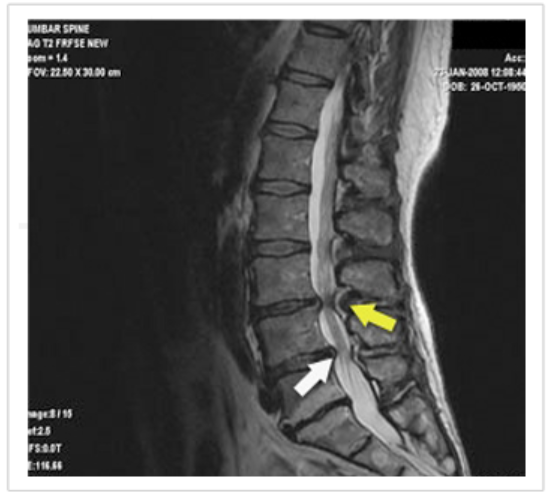

척추관협착증은 퇴행성디스크와 함께 대표적인 퇴행성척추질환으로 척추의 퇴행이 오래 진행되어 인대가 두꺼워지고 부으면 신경구멍이 좁아지며 척추관협착증이 유발됩니다.

요통과 하지통을 동반하기 때문에 허리디스크(요추추간판탈출증)와 혼동되기도 하지만 몇 가지 증상에서 두 질환간의 명확한 차이가 존재하므로 구분하는데 어려움은 없습니다.

척추관 협착증은 요추부에 주로 많이 발생하는데, 보통 척추관 협착증(척추강 협착증)이라 하는 것은 요추 척추관 협착증(요추관 협착증)이 정확한 표현이며 이러한 협착증이 경추 부위에 발생하면 경추 척추관 협착증(경추관 협착증)이라고 합니다.

척추의 뼈 사이에 있는 탄력적인 추간 조직을 추간판(디스크)이라 하는데, 내부는 부드러운 수핵으로 되어있고 겉은 단단한 섬유륜으로 싸여있습니다.

보통 30세 이후부터 수핵과 섬유륜에 퇴행성 변화가 시작되어 이로 인해 추간판이 척추에 부착된 부위가 떨어져 골극(가시 같은 모양으로 뼈가 튀어나온 것)이 형성됩니다.

동시에 척추관을 구성하는 후관절 돌기, 추궁, 황색인대 등에서도 변성이 오면서 두꺼워져서 척추관 전후, 좌우 사방이 좁아지며 여기에 척추가 전방 또는 후방으로 휘어 척수와 신경근을 직접 누르고 혈류장애를 일으켜 증상이 나타나는 것입니다.